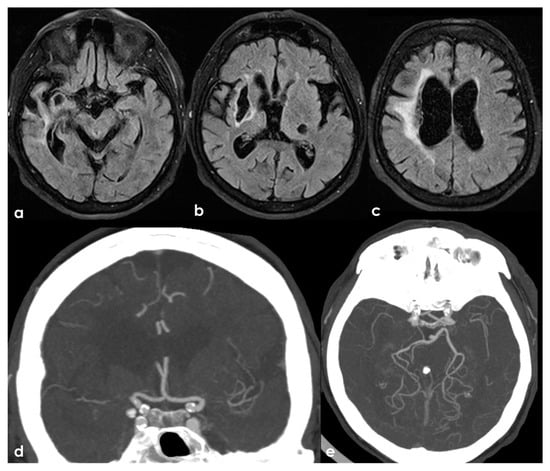

Figure 3.

A remote ischemic lesion in the right MCA territory is illustrated in the axial FLAIR sequence of the brain MRI (panel (a–c)) with the corresponding vascular imaging on a CT angiography with minimum intensity projection/multiplanar reconstruction (MIP/MPR) (panel (d,e)) in the coronal and axial plane, respectively. M1 MCA on both sides is occluded with a tiny network of small vessels partially contributing to supply M2 MCA.